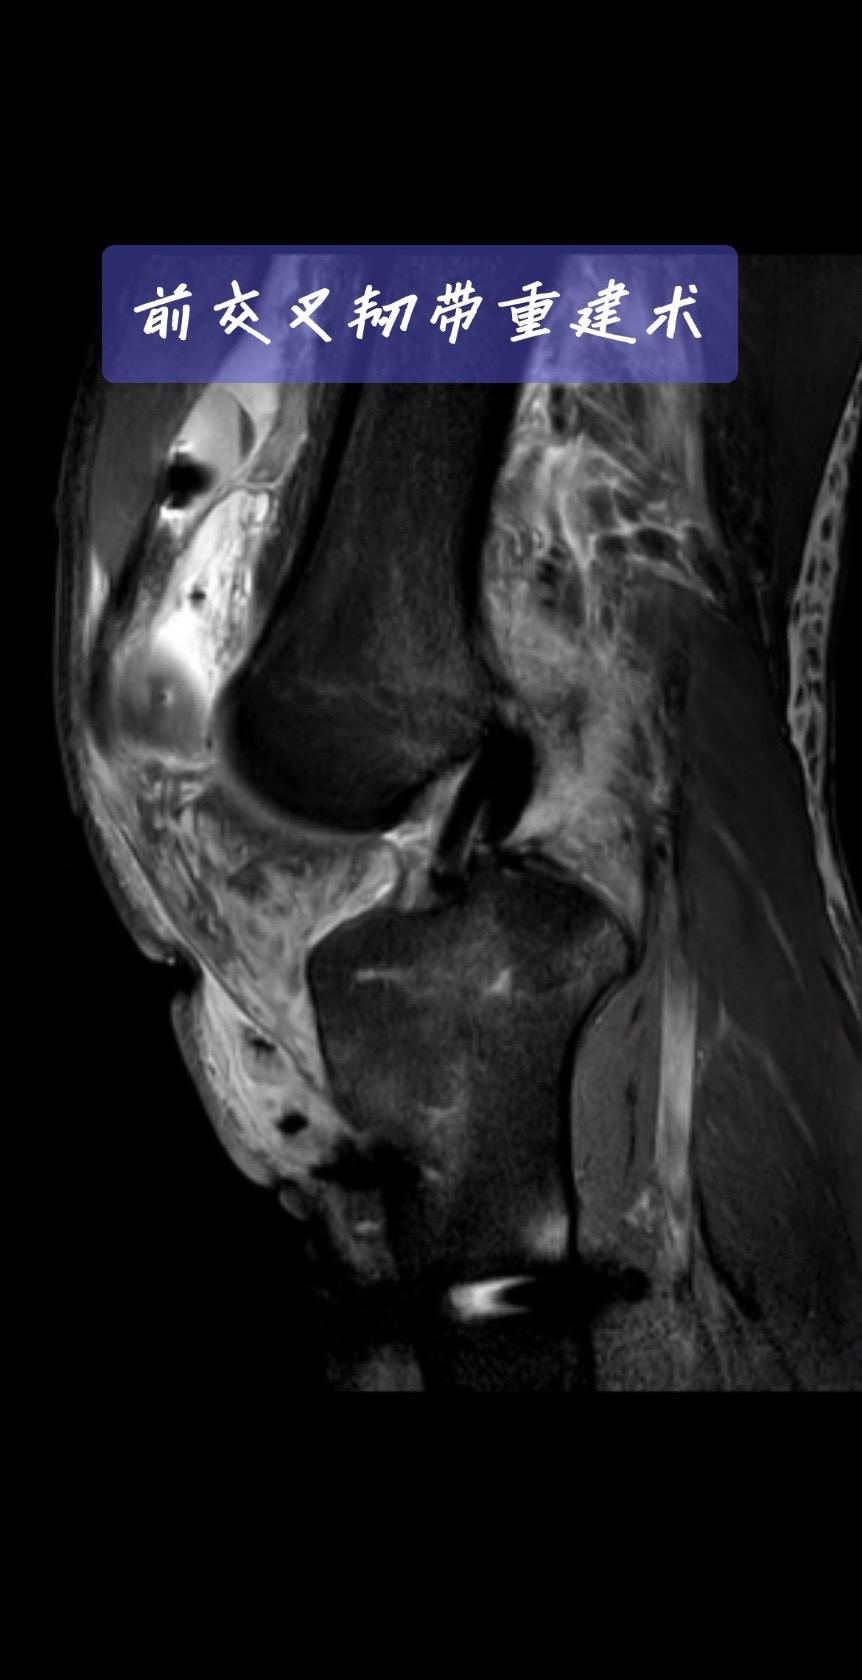

前交叉韧带重建。一台成功的前交叉韧带重建,关键在于“精准”二字。术后CT、MRI复查,就是我们医生的“成绩单”。前交叉韧带重建 运动医学 膝关节术后 骨科医生 医学科普